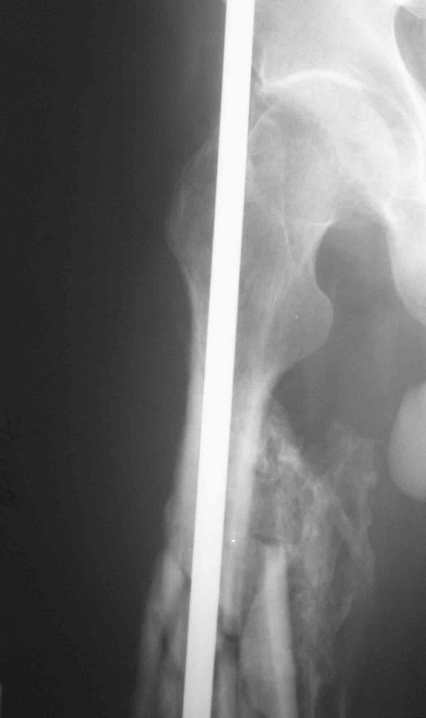

Re: 32- летний пациент с переломами обоих бедер после неудачного оперативного и консервативного лечения.

Иллюстрации к сообщению

а) Наложить односторонный одноплоскостной аппарат внешней фиксации на бедро, синтезированное стерднем ЦИТО. Сам стержень "забить" глубже. Стнржни провести непросто, но вполне реально. По стержню делается дистракция в аппарате (Методика из немецкого журнала ортопедия, 1996 год).

Уважаемый Антон.Исходя из Вашего материального положения!! и наличия хорошего, грубого омозоления, равности длины конечностей и судя по снимкам не очень выраженной антекурвации, но выраженной контрактуры коленных суставов: чтоб не упустить время разработки суставов и активизировать больного, необходимо справа удалить стержень, рассверлить канал и произвести ЗИМО более толстым неблокир. стержнем т.к. на этом уровне можно получить устойчивый остеосинтез, после чего активизировать и дозированная, упорная ЛФК, а дальше после восстановления функции ,время покажеть.

Cyдя по представленным рентгенограммам оба бедра консолидированы. Необходима активная разработка движений в коленных суставах. Хотелось бы увидеть фотоснимки больного ( нижних конечностей спереди и сбоку). Если стержень мешает разработке движений то его надо удалить.